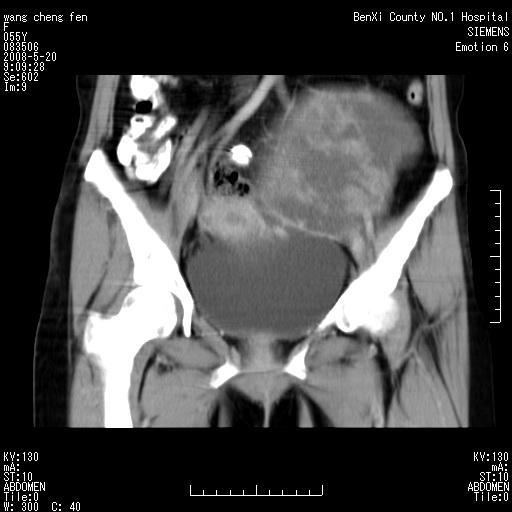

标题: CT3539:盆腔巨大肿瘤增强 [打印本页]

标题: CT3539:盆腔巨大肿瘤增强

女、绝经后阴道流血3个月

左侧附件区巨大囊实性病灶,边缘光整,病灶囊壁较厚,增强示囊壁及实性部分明显强化,强化呈度与宫体实质大致相同,宫腔积液征像,未见盆腔积液等其他异常,考虑左侧卵巢囊腺癌,不除外囊腺瘤及浆膜下肌瘤坏死

宫颈好像也有问题吧,大家在仔细看看,另外彩超回报为卵巢占位。建议ct。

支持浆膜下子宫肌瘤.之前由于网络原因未看全图片,现在重看,宫颈见一类圆形低密度影,增强轻度强化,低于肌层强化,宫腔扩大,考虑宫颈癌伴宫腔积液可能性大.

1,宫颈部占位,宫颈癌?2,左侧附件区囊实性占位,界较清,实质部分强化明显。考虑浆膜下或阔韧带肌瘤囊变可能大。囊腺类肿瘤不除外。